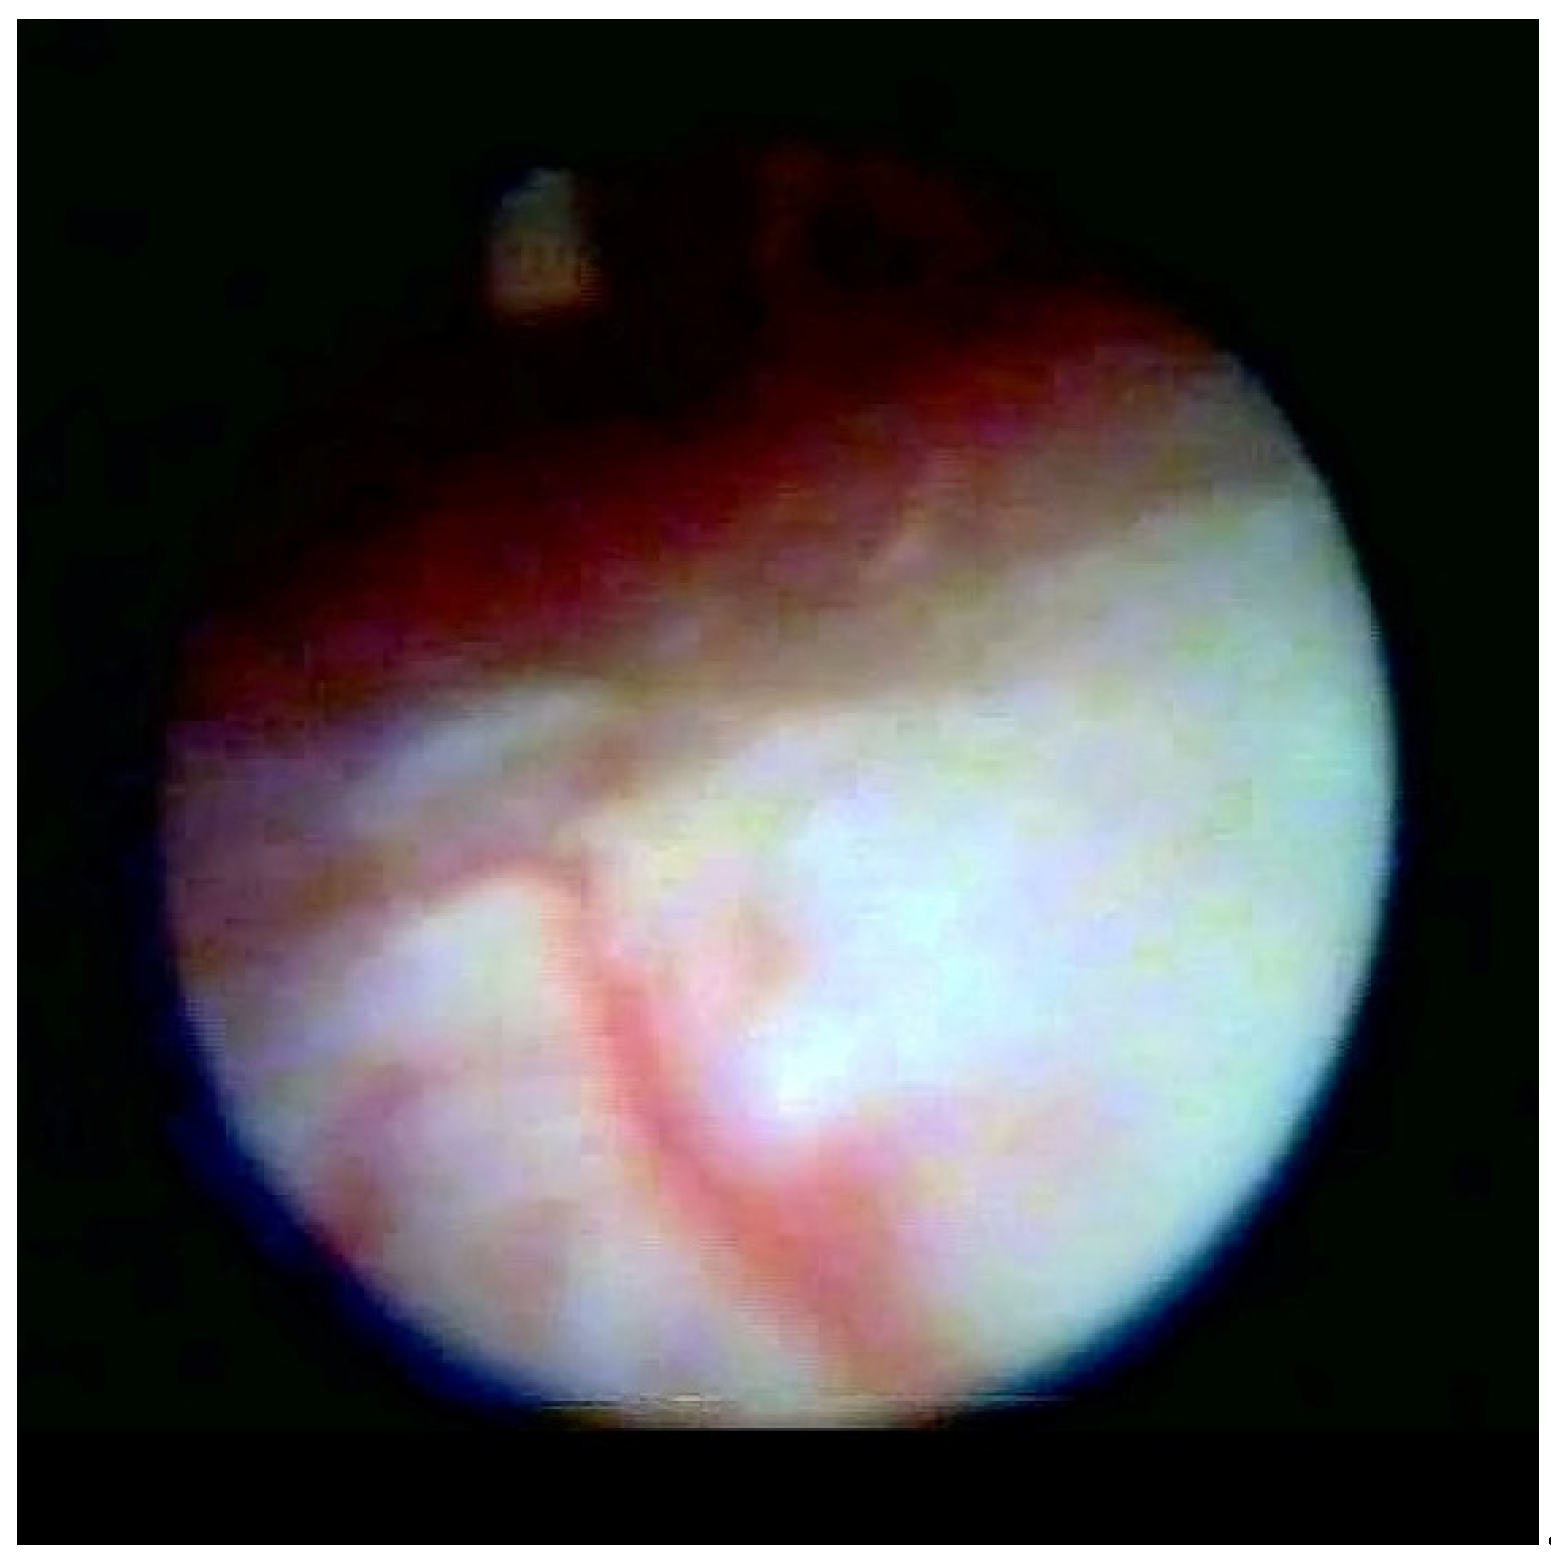

Figure 2 shows the lifting of the meningeal dura for dural mobility abnormalities with an underlying lifting of the spinal root, which determines a pseudo-lifting of the dura, potentially resulting in a false diagnostic radiology interpretation of a median ligament. Moreover, the presence of a Fogarty catheter inside the bed of the dura in the midline causes lifting of the dura mater in relation to the root below, which can mimic a false longitudinal ligament in radiodiagnostic imaging (Figure 3). Morphological analysis of the pathological spaces also showed that, in these cases, no segmentation occurred. The left side of Figure 4 shows a fibrotic septum grafted on the dura. However, underlying dural bases exhibit no segmentation.

The presence of fibrotic septa, without apparent cause and limited to a single vertebral body, was detected in a few cases. In our video review, we found one patient with a segmentation-like feature. This appeared to be the result of a raising of the dura due to loss of its elasticity and the presence of a hyperpressure on the dural cloth (Figure 2), as previously reported [16].

In accordance with Hogan [9], we believe that the membrane could be attributed to raising of the dural cloth due to pressure secondary to the use of rigid instruments on the dura (Figure 3). Moreover, in the presence of tractions secondary to pathological events (such as post-surgical or post-inflammatory fibrosis) on the dura mater, the membrane could be raised by generating, with its “sail” shape, a segmentation-like feature [16] (Figure 4). Hogan claimed that in addition to the absence of any “fibrous barrier across the intervertebral neural canals” a narrow fibrous band could sometimes be seen adjacetn to the superior edge of pedicle epidural space … and epidural space is widely open on its lateral aspect” [8]. Asato published a paper indicating that no obstacle existed to the spread of epidural solution due to a median epidural septum, and the epidurography, performed in seven patients with unilateral epidural block, showed that the cause of the unilateral block was the placement of the catheter into the anterior or transforaminal epidural space [18]. Transversal segmentation, which divides the space into two sections, can be present in subjects with diseases secondary to chronic polyfactorial stenosis or where previous spinal surgery justifies abnormalities in fluid distribution, based on the CT findings by Savolaine [7].

Figure 2. Normal dura, root lifting.